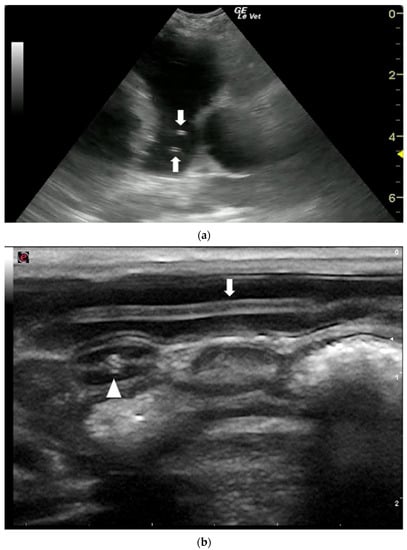

- Venco, L.; Colaneri, G.; Formaggini, L.; De Franco, M.; Rishniw, M. Utility of thoracic ultrasonography in a rapid diagnosis of angiostrongylosis in young dogs presenting with respiratory distress. Vet. J. 2021, 271, 105649. [Google Scholar] [CrossRef]

- Wigger, A.; Peppler, C.; Kramer, M. Ultrasonographic appearance of intestinal roundworms in a dog and a cat. Vet. Rec. 2007, 161, 200–201. [Google Scholar] [CrossRef]